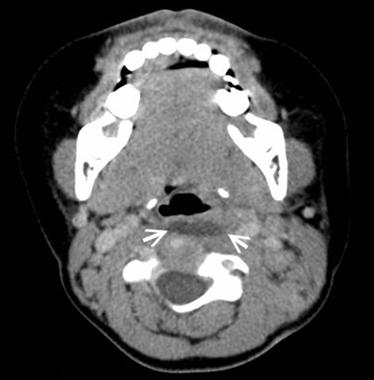

這題的關鍵在於辨識兒童急性發燒、吞嚥困難,加上電腦斷層(CT)影像中,咽喉後方出現一個邊緣顯影(rim enhancement)的液體聚積(fluid collection),這強烈指向感染性膿瘍。